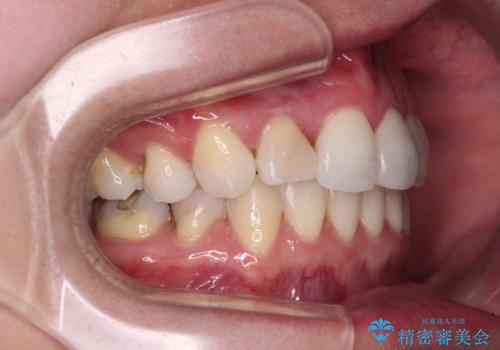

期間はかかったものの、口元の張り出し感や歯のデコボコが解消され、患者様には大変満足していただけました。

治療期間の目安は3年~3年半でしたが、咬み合わせにより上顎のスペースがなかかな閉じきらず、治療期間が長期化してしまいました。